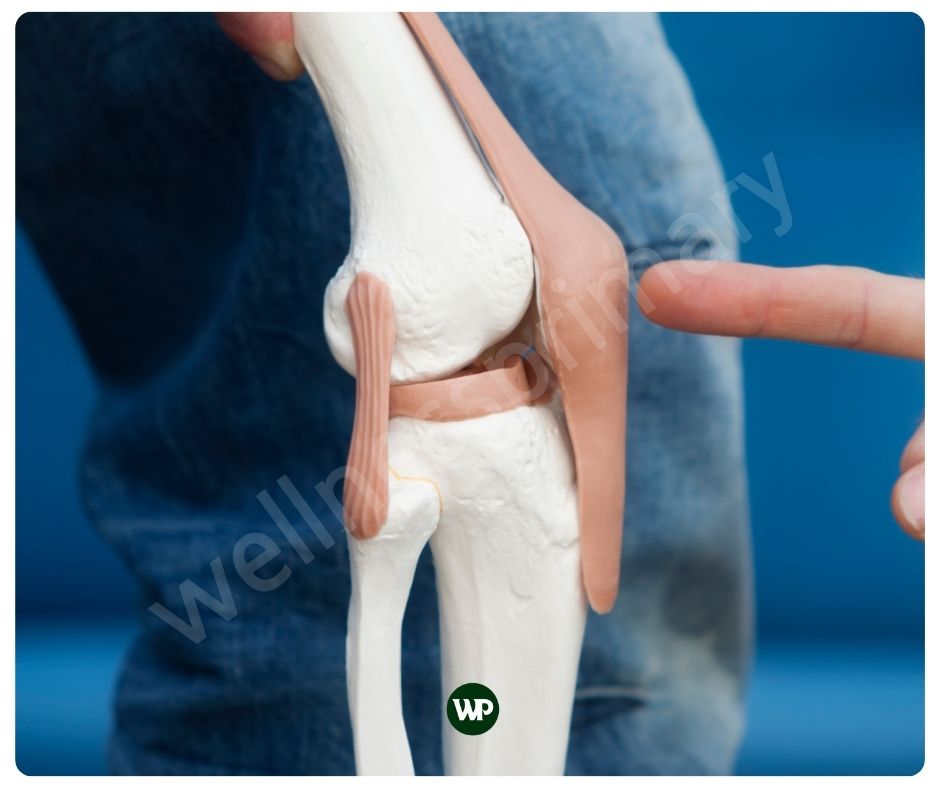

인간의 연골의 두께는 무릎의 대퇴골 연골의 경우 약 3mm에서 4mm 정도로 가장 두껍습니다. 어깨 관절 연골은 약 1mm~2mm에 불과하지요. 연골은 우리의 움직임을 위해 매우 중요한 역할을 하지만 실제로 매우 얇습니다. 그래서 가능한 빨리 연골 보호에 신경을 써야 합니다. 콘드로이친 효능은 연골의 손상을 예방하며, 이는 특히 연령 증가에 따른 연골 퇴화를 막는 데 중요한 역할을 합니다. 콘드로이친은 이미 손상된 연골의 경우, 그 회복을 돕고, 연골 세포의 재생을 촉진하는 매우 중요한 역할을 합니다.

콘드로이친은 연골 조직에 존재하는 물질인데요. 주로 관절과 뼈의 건강에 중요한 역할을 합니다. 콘드로이친은 연골 내에 존재하는 중요한 글리코사미노글리칸의 일종으로, 주로 연골, 뼈, 힘줄, 인대 등에 많이 있습니다. 연골의 주요 구성 요소인 콘드로이친은, 관절의 부드러운 움직임을 도와주며 충격을 흡수해 통증을 완화해 줍니다. 또한 당과 단백질의 복합체인 프로테오글리칸의 일부로, 연골의 탄력성을 높이는데에도 도움이 됩니다. 주로 상어와 소의 연골에서 추출하여 영양제로 섭취할 수 있습니다.